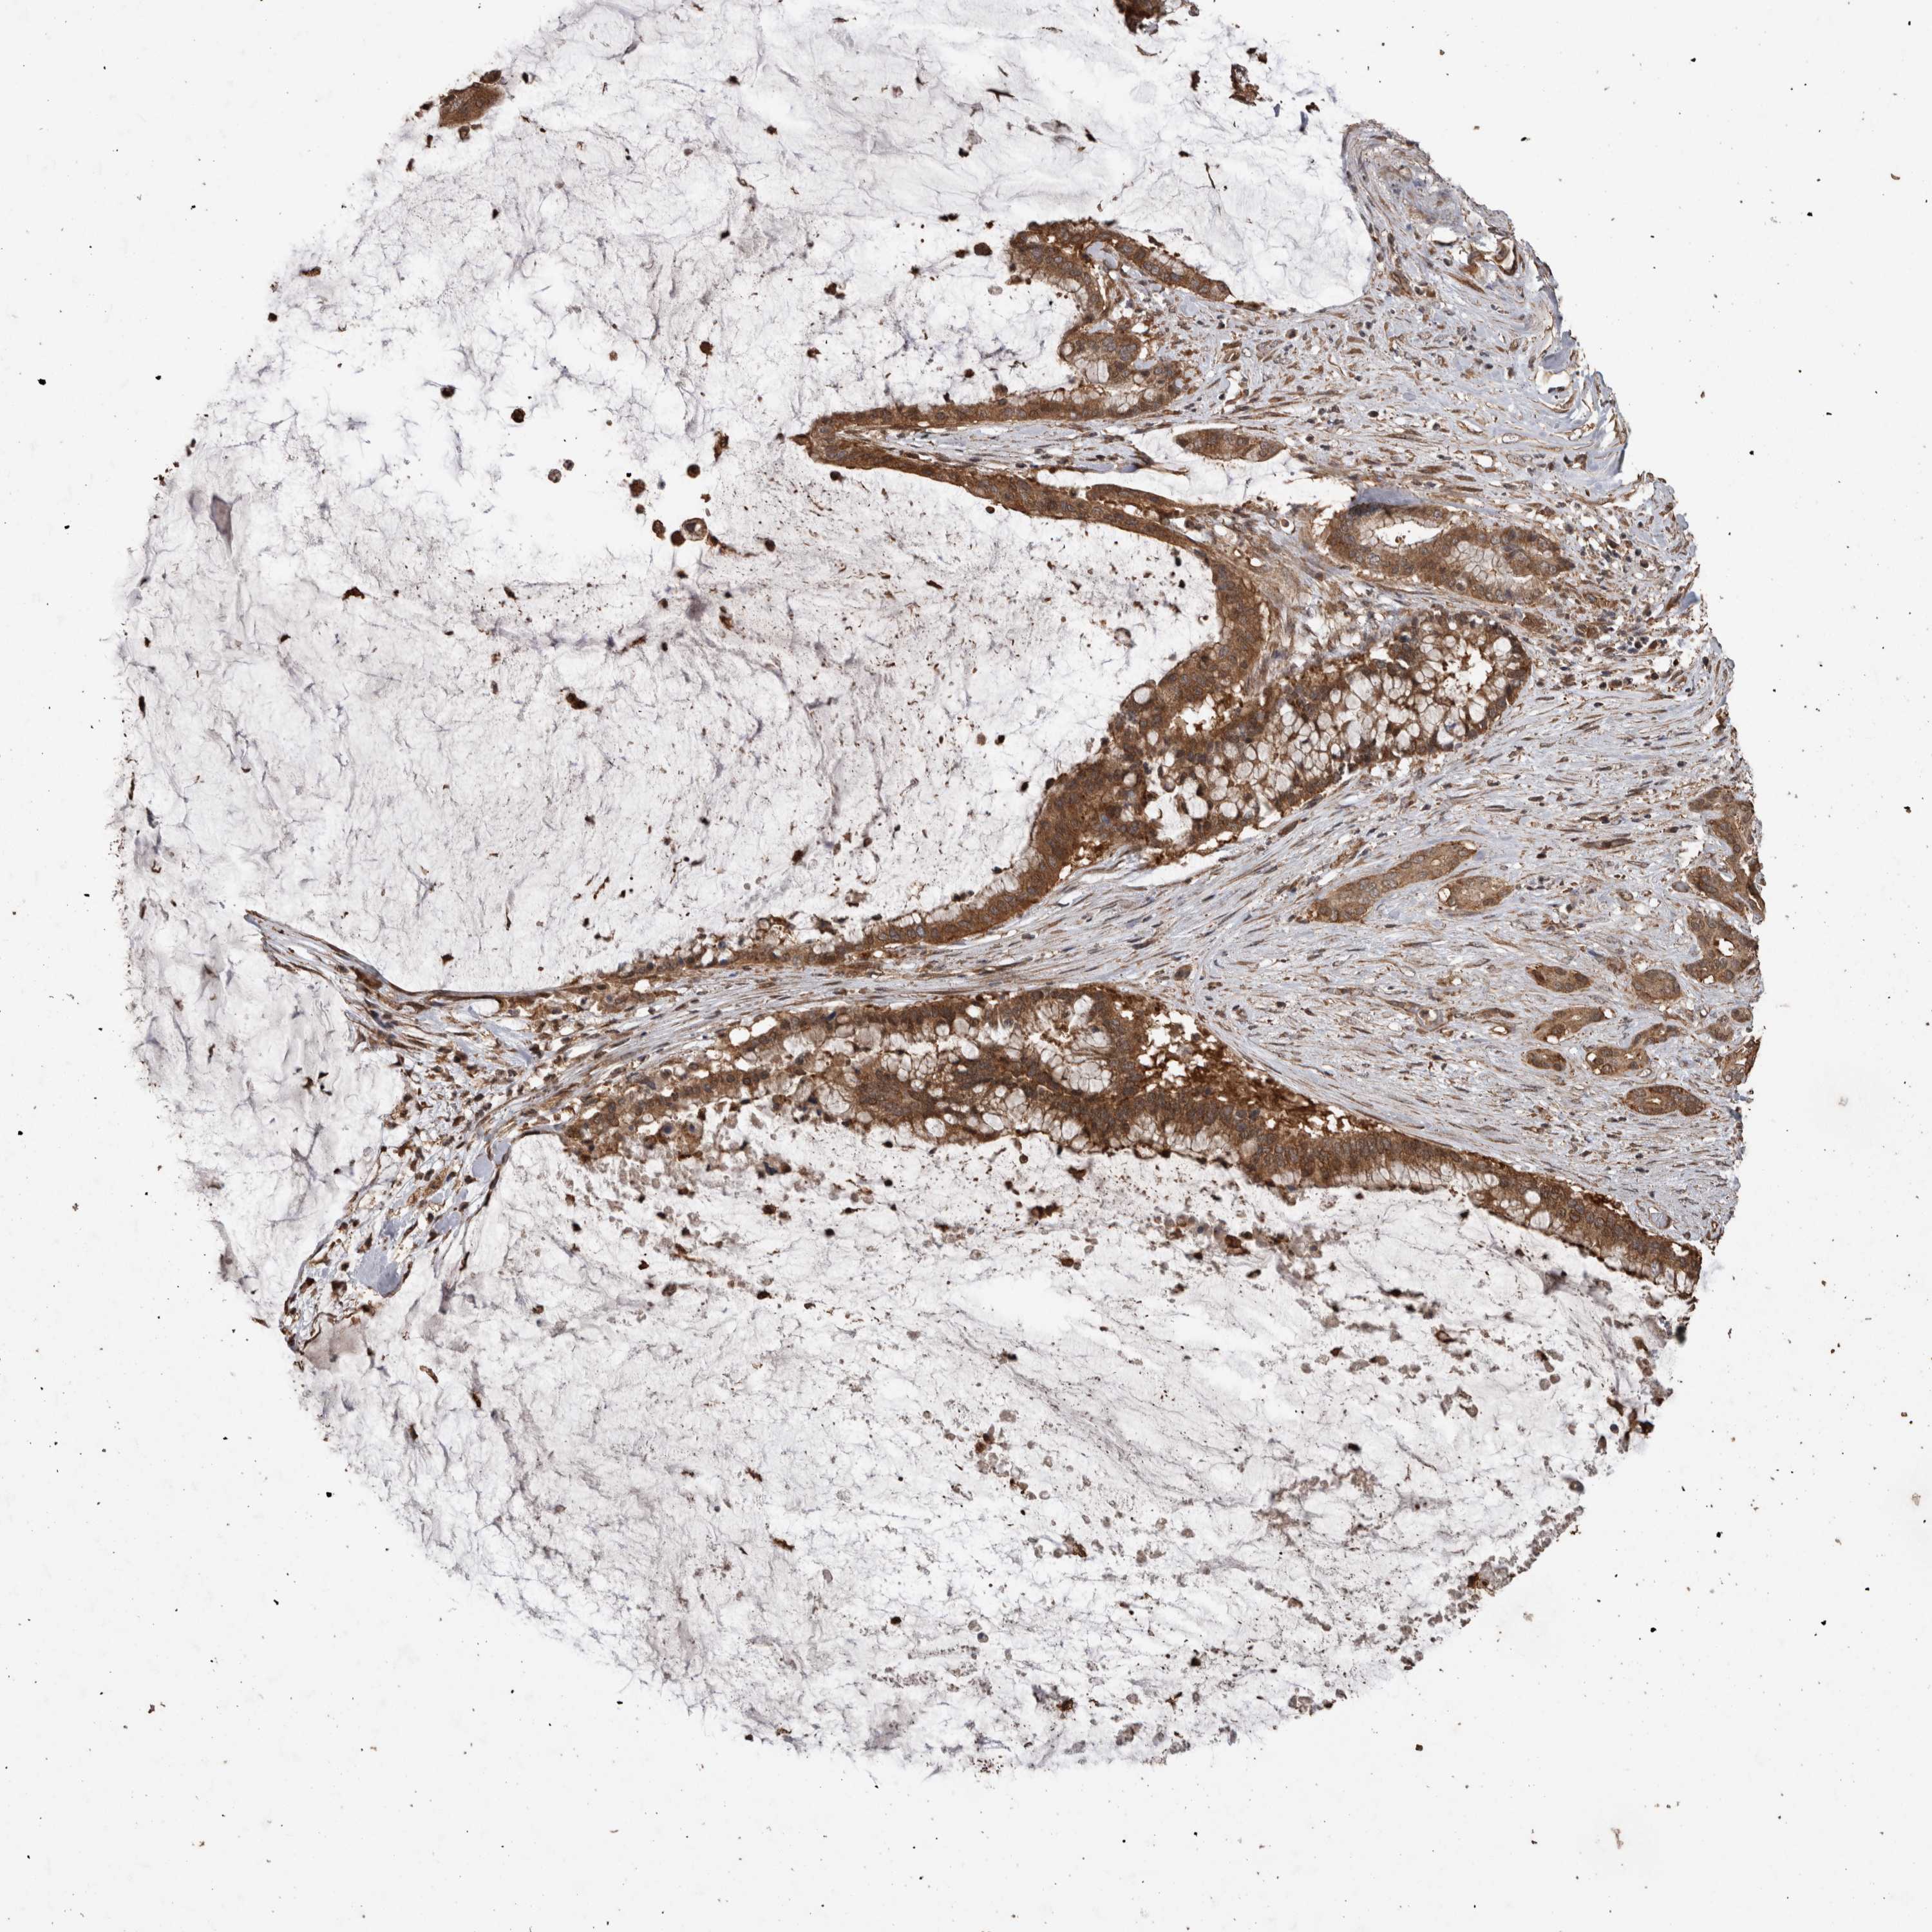

PANCREATIC CANCER - Protein expressioni

A mouse-over function shows sample information and annotation data. Click on an image to view it in a full screen mode. Samples can be filtered based on level of antibody staining by selecting one or several of the following categories: high, medium, low and not detected. The assay and annotation is described here.

Antibody stainingi

Antibody staining in the annotated cell types in the current human tissue is reported as not detected, low, medium, or high, based on conventional immunohistochemistry profiling in selected tissues. This score is based on the combination of the staining intensity and fraction of stained cells.

Each image is clickable and will lead to virtual microscopy that enables deeper exploration of all samples and also displays staining intensity scores, fraction scores and subcellular localization as well as patient and tissue information for each sample.

Antibody HPA001931

Antibody CAB026191

Staining

High

Medium

Low

Not detected

Intensity

Strong

Moderate

Weak

Negative

Quantity

>75%

75%-25%

<25%

None

Location

Nuclear

Cytoplasmic/membranous

Cytoplasmic/membranous,nuclear

Adenocarcinoma, NOS